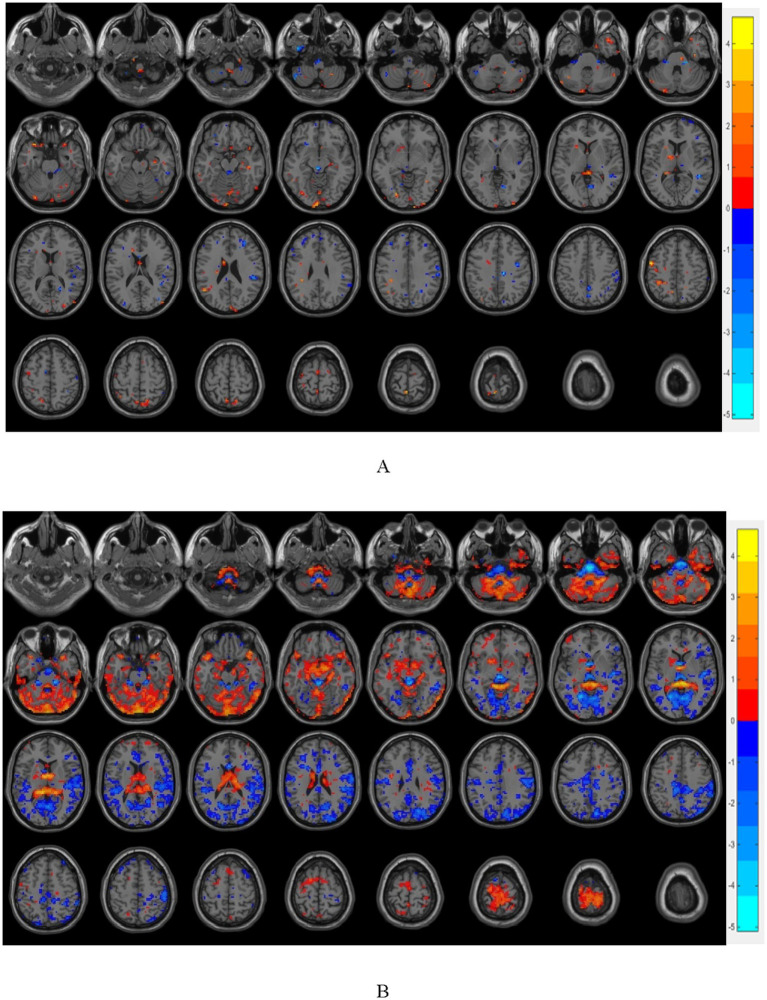

Results: Compared with the OB and HC groups, the T2DM group showed a significant reduction in cortical thickness in the bilateral superior frontal gyrus, inferior frontal gyrus orbital region, and the lower part of the right middle frontal gyrus, and the functional connectivity of the prefrontal cortex showed a significant trend of enhancement. Meanwhile, compared with the HC group, the T2DM group showed a significant decrease in FA (fractional anisotropy) values in the midline region of the orbitofrontal cortex bilaterally, and the left inferior frontal gyrus orbital region also showed a significant decrease in FA values, whereas AD (axial diffusivity), MD (mean diffusivity), and RD (radial diffusivity) increased significantly.

Data conclusion: T2DM patients have significant alterations in gray matter structure, brain white matter integrity and brain function, and most of the brain regions with significant differences are in the prefrontal cortex, which confirms that the abnormal desire to ingest in T2DM patients is closely related to the functional alterations of the reward system, and that observing the brain function and structural changes of the reward loop through imaging may help in the early diagnosis and treatment of overweight/obese T2DM patients.